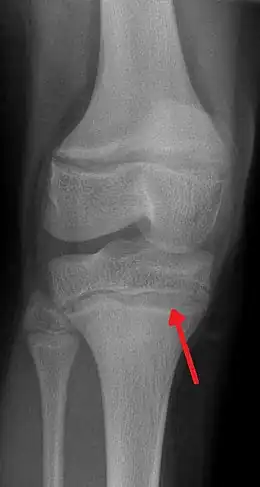

- dans les cas d'intoxication forte et/ou chronique, apparition d'un liseré grisâtre ou bleuâtre sur les gencives au niveau du collet des incisives et/ou canines, dit « Liseré de Burton » (très rare chez le jeune enfant, plus fréquent chez l'adulte gravement intoxiqué), taches jugales de Gubler[176], et apparition sur les radiographies osseuses d'une ligne blanche parfois dite métaphyséale sur les os longs, à la limite de l'os creux (diaphyse) et la zone de production du cartilage (ex. : image en haut à droite)[177] ;